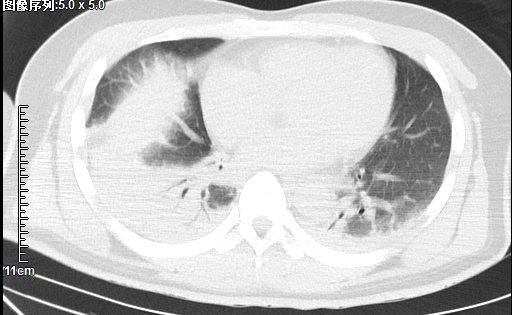

完善的CT检查显示:双肺渗出性改变伴部分实变,立即联系呼吸与危重症医学科王婷婷副主任为患者床旁行支气管镜检查,发现双肺下叶支气管被脓痰不完全阻塞,给予灌洗及对症处理。